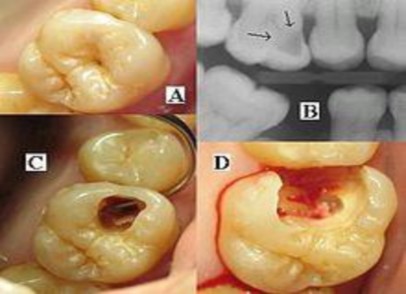

Hình 1.1. Biểu hiện của sâu răng

(A) Một lỗ sâu răng nhìn thấy được trên bề mặt của một chiếc răng.

(B) Chụp X quang cho thấy một khu vực khử khoáng trong vùng ngà (mũi tên).

(C) Một lỗ được phát hiện ở bên cạnh răng khi bắt đầu phá lỗ sâu răng.

(D) Tất cả các phần sâu răng được loại bỏ.

Nguồn: https://vi.wikipedia.org/wiki/S%C3%A2u_r%C4%83ng